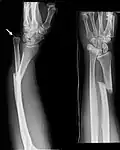

Unter einer Galeazzi-Fraktur (nach dem italienischen Chirurgen Riccardo Galeazzi, 1866 bis 1952) versteht man den Bruch des Radius im Schaftbereich oder handgelenksnah mit Riss der Membrana interossea und der Bandverbindung mit der Ulna (Elle) – dem distalen Radioulnargelenk (DRUG) und dadurch verursachter (Sub-)Luxation (Verrenkung) der Elle. Verursacht wird eine Galeazzi-Fraktur durch Gewalteinwirkung auf den auswärts gedrehten Unterarm.

Mit etwa 3 bis 6 % der Unterarmfrakturen sind Galeazzifrakturen recht selten. Bei isolierten Radiusschaftfrakturen muss jedoch immer nach derartigen Begleitverletzungen gesucht werden, da eine übersehene und unzureichend behandelte Verletzung im DRUG zu hochgradigen funktionellen Einbußen bis hin zum Verlust der Drehfähigkeit des Unterarmes oder einer durch Instabilität verursachten Kraftlosigkeit im Handgelenk führen kann.